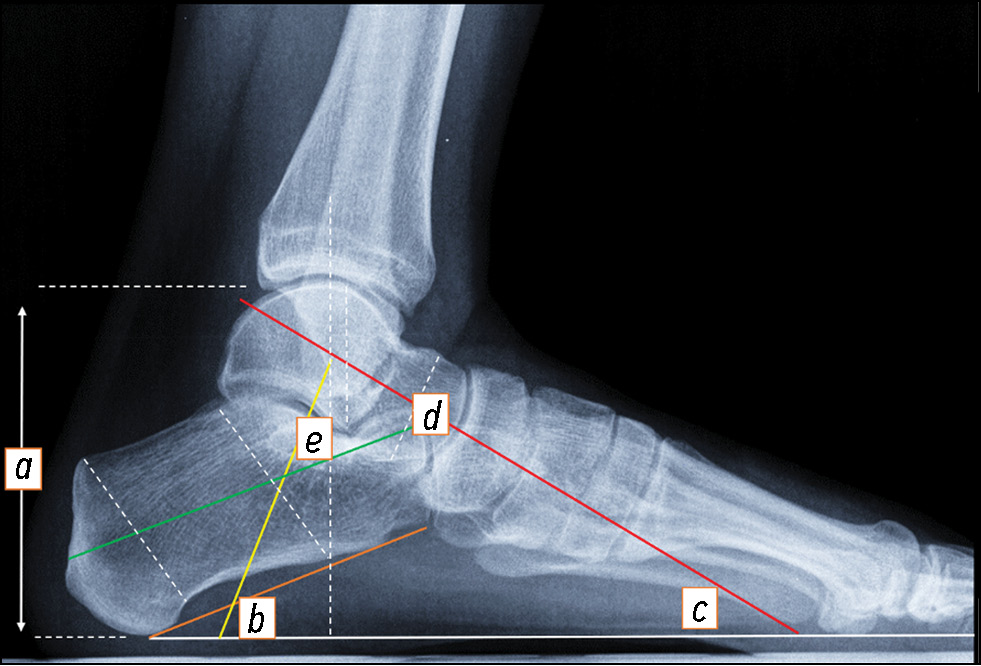

Все пациенты, принявшие участие в исследовании, были вызваны на контрольный осмотр через 8 и 14 недель после операции. Через 2 мес. после операции пациенты проходили КТ-исследование оперированной стопы, где основным показателем была перестройка аутоплантатов с начальными явлениями формирования таранно-пяточного анкилоза. Через 3,5 мес. после операции выполнялись нагрузочные рентгенограммы стоп в трёх проекциях. На рентгенограммах стоп в боковой проекции оценивались следующие параметры: высота таранной и пяточной кости, мм; угол наклона пяточной кости, мм; угол наклона пяточной кости, градусы; угол инклинации таранной кости, градусы; угол наклона таранной кости, градусы; таранно-пяточный угол, градусы (рис. 8). Большеберцово-таранно-пяточное положение и его соосность оценивались на функциональных рентгенограммах стоп в проекции Зальцмана.

Рис. 8. Рентгенограмма нормальной стопы в боковой проекции с нагрузкой, демонстрирующая рентгенографические параметры заднего отдела стопы. a — высота таранной и пяточной кости, b — угол наклона пяточной кости, c — угол инклинации таранной кости, d — угол наклона таранной кости, e — таранно-пяточный угол.

Fig. 8. Weight-bearing lateral radiograph of a normal foot demonstrating radiographic measurements for hindfoot alignment. a — talocalcaneal height, b — calcaneal pitch angle, c — talar inclination angle, d — talus declination angle, e — lateral talocalcaneal angle.